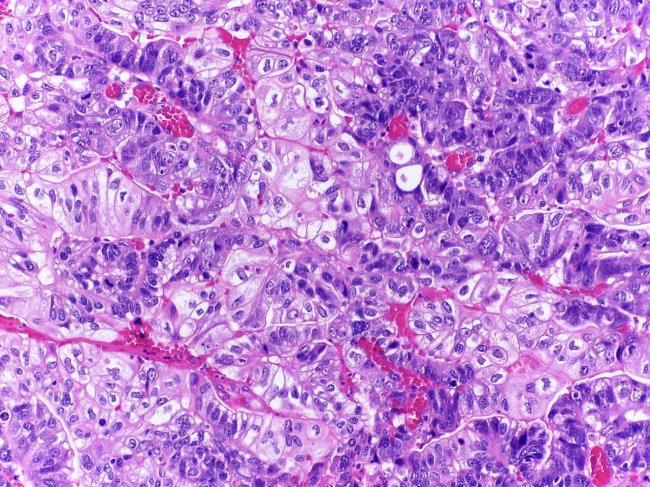

- Anatomia Patológica

Os meios de diagnóstico protocolados para a confirmação dos tumores dos digestivo alto são:

- Endoscopia digestiva alta

- Biópsia gástrica

No caso dos tumores hepatobiliopancreáticos, estão prorocolados os seguintes meios complementares de diagnóstico:

- Biopsia hepática

- Biopsia aspirativa percutânea